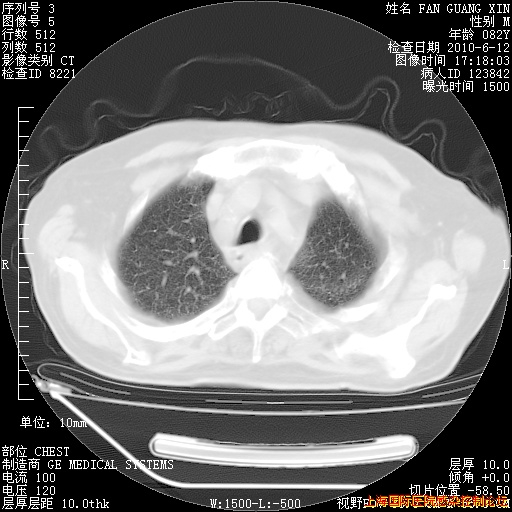

今天复查CT

今天CT

整整相隔30天的肺部CT好像有所好转啊。甲强龙减量第3天,需要观察体温。